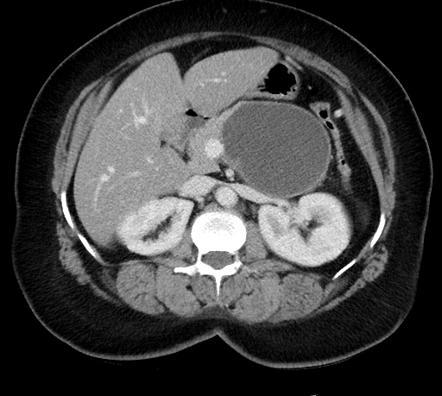

64M w/hx of cirrhosis. P/w acute RUQ pain and this lesion had a pseudoaneurysm

HCC

Hypervascular liver mass in pt w/cirrhosis that spontaneously bleeds is essentially diagnostic of HCC

—> mets dont usually go to cirrhotic livers